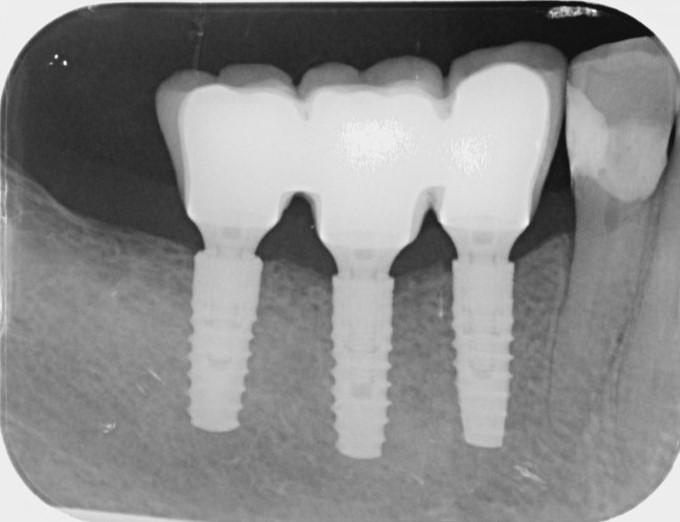

The X-ray check after fitting the final restoration.